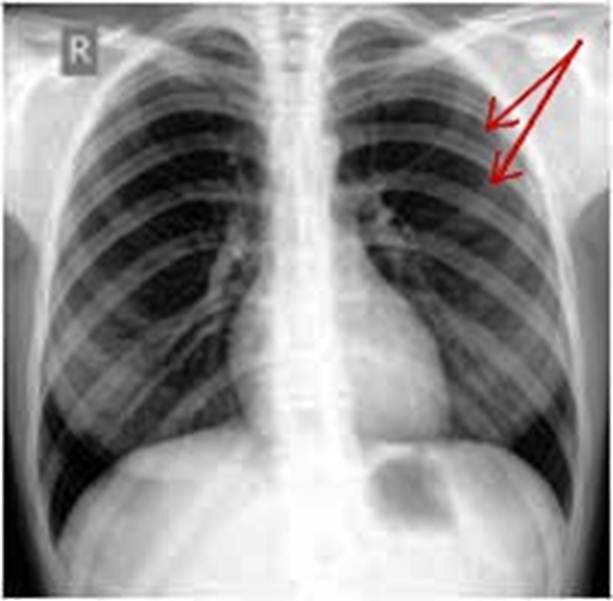

S: Стрелки указывают на сostae verae (латинский язык).

S: Стрелки указывают на сostae fluctuantes (латинский язык).

S: Стрелки указывают на сostae spuriae (латинский язык).

S: Стрелки указывают на cortilagines costales (латинский язык).

S: Цифрой 3 обозначена верхняя апертура грудной клетки (русский язык).

S: Стрелки указывают на spatia intercostalia (латинский язык).

S: Стрелки указывают на anguli costae

S: Стрелки указывают на spatia intercostalia